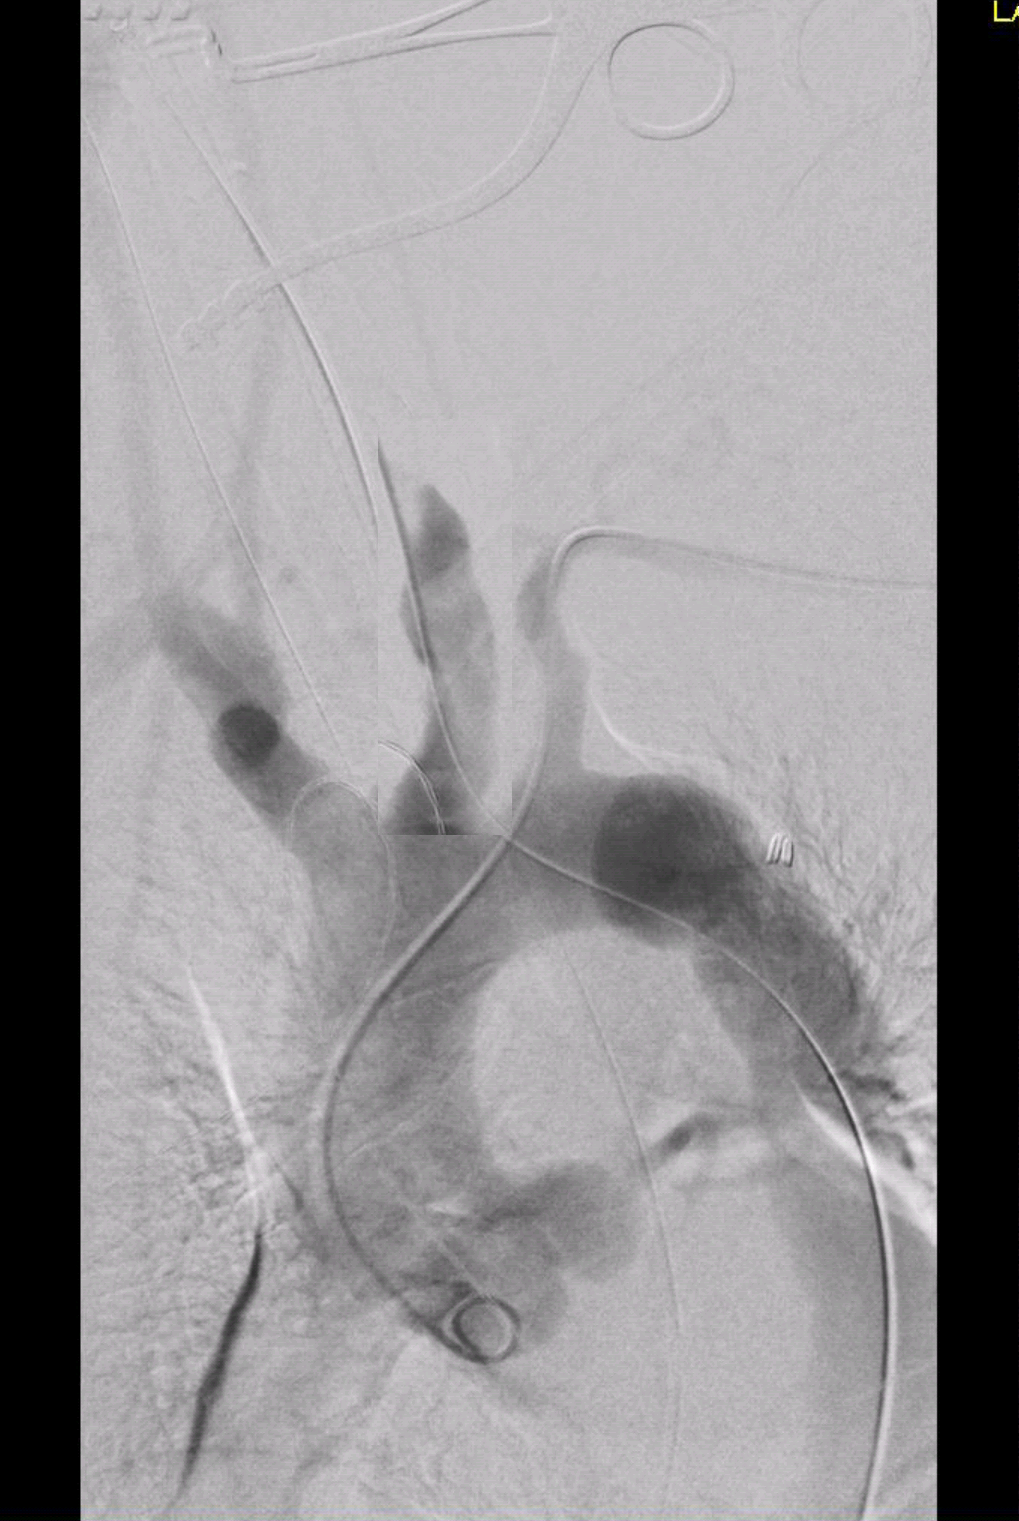

The predeployment arteriogram identified fluoroscopic clues to deployment.

In this patient’s case, the tip of the ET tube provided an excellent reference. (see above composite arteriogram).

Deployment was satisfactory. The arteriotomy, a transverse one I had made to avoid a tear in the thickened, chronically diseased artery, was repaired with running monofilament suture after flushing. The patient did have some oozing because of being on Plavix, but a drain was unnecessary. He awoke neurologically intact and was dimissed on POD#2.